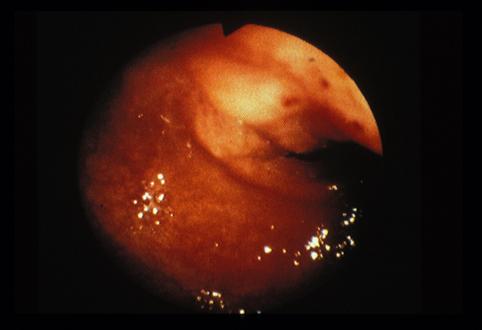

질환(병리주체)의 분류 종양양 병변/이소성 점막

부위(장기별) 대장/S상

검사방법 내시경

종양의 최대경(밀리미터) 40이상